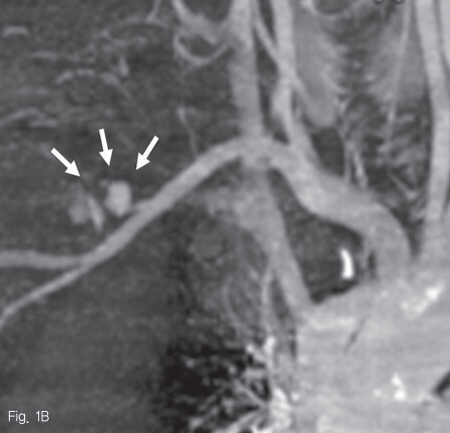

CT 동맥 조영술의 동맥기와 지연기에 우쇄골하동맥 원위부의 전외측에 현성 출혈로 판단되는 조영제의 혈관외유출 및 이로 인한 가성 동맥류가 관찰되었다. 그 주변과 우측 액와부에 걸쳐 많은 양의 혈종이 보였으며, 이로 인해 우측 대흉근이 앞쪽으로 밀려있었다. 또한 이와 인접한 우외측 흉벽의 피부 및 피하부종이 동반되었다 (Fig. 1A, B).

Fig 1B

Contrast enhanced CT angiography A. and maximum intensity projection image B. show active extravasation of contrast media (A, B: white arrows) from anterolateral aspect of right subclavian artery (black arrow, A), forming a large hematoma in the right anterolateral chest wall and axilla (asterik, A)